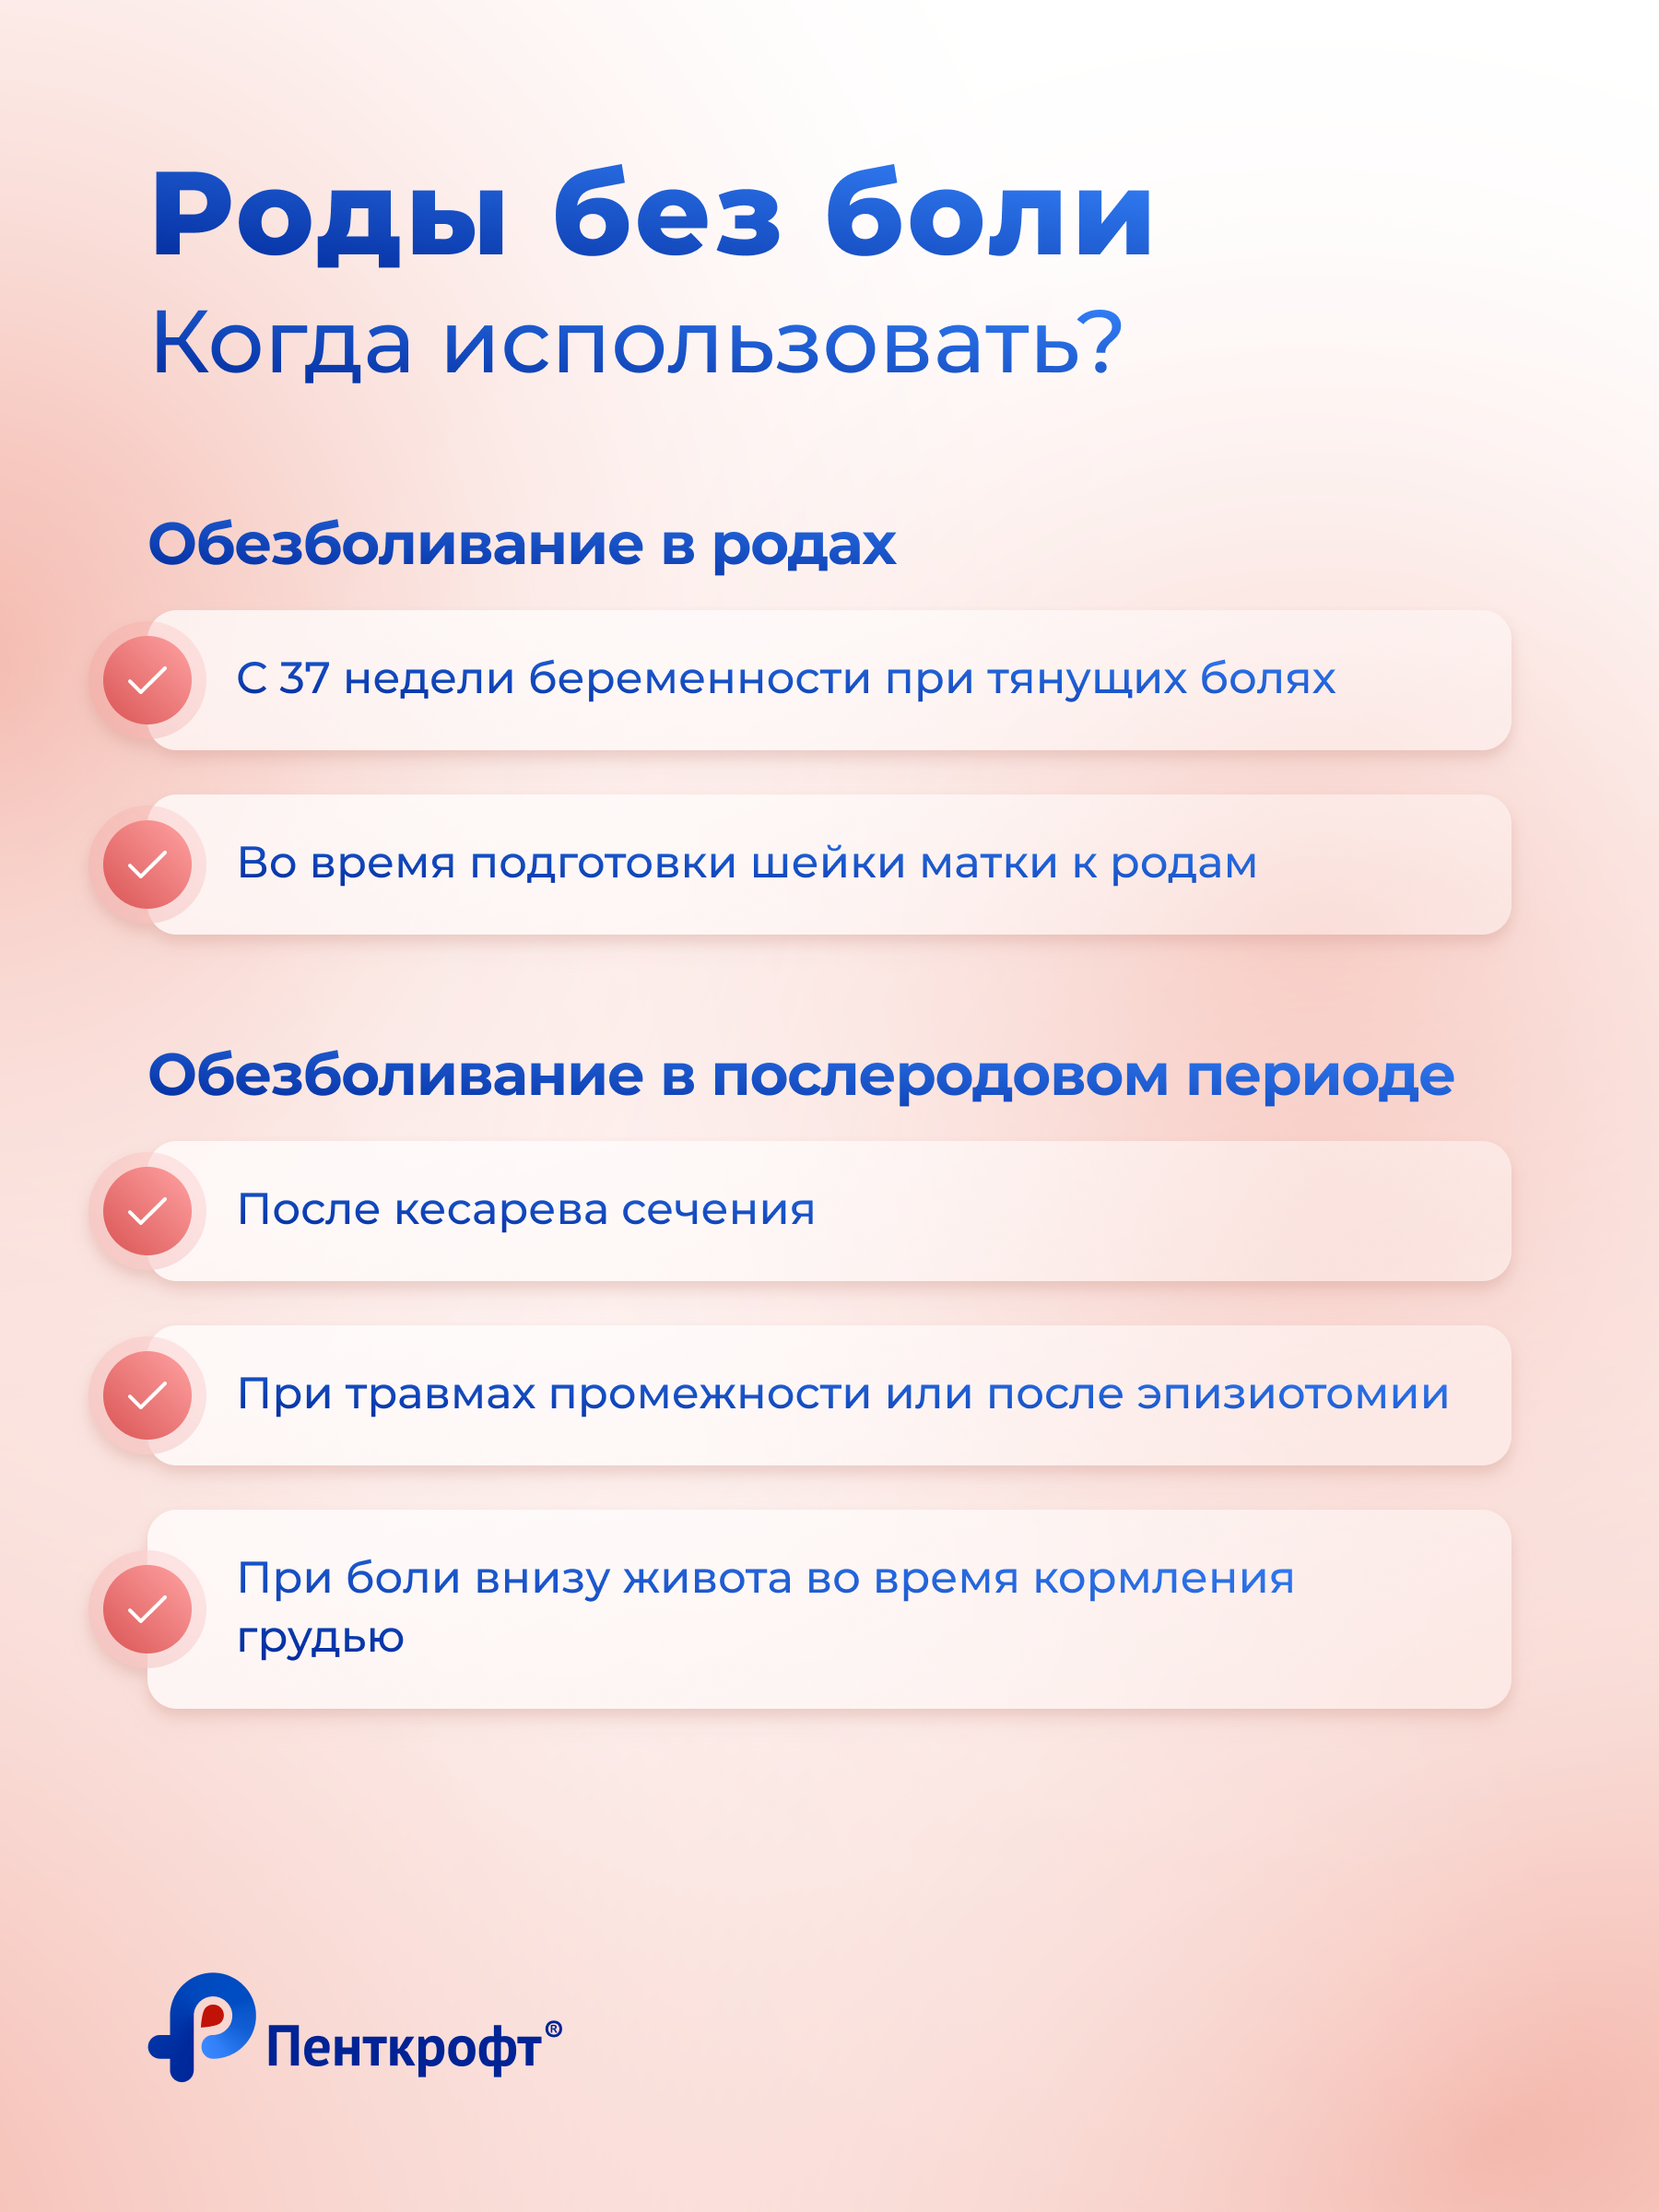

Это верное решение. Электростимулятор Perfect mama+ для снятия боли в родах и в послеродовом периоде (пр-во Англия) – это инновационный медицинский прибор, позволяющий роженице управлять болью в родах. Прибор блокирует передачу нервного импульса в центральную нервную систему от матки и промежности, таким образом снижая болевые ощущения, а также стимулирует двигательные нервы, создавая небольшие повторяющиеся сокращения мышц. Это воспринимается мозгом как упражнение и способствует выделению эндорфинов - естественных болеутоляющих средств [17].

Прибор зарегистрирован в РФ как медицинское изделие, прошел все исследования по безопасности (РУ № РЗН 2023/20954 от 25.08.2023г.) и успешно прошел клинические исследования и апробацию в ведущих родильных домах России. Согласно результатам исследований, 91% женщин, использовавших Perfect mama+ во время родов, отметили снижение интенсивности боли в 2 раза (по ВАШ). Более того, длительность родов сократилась на 2 часа за счет снижения продолжительности потужного периода. Пациентки значимо выше отмечали удовлетворенность от родов с использованием Perfect mama+ по сравнению с эпидуральной анестезией (по опроснику удовлетворенности) [18].

3 уровня стимуляции Perfect mama+ обеспечивают точное управление болевыми ощущениями. Пользоваться прибором легко и просто и дома, и в роддоме благодаря большому экрану с подсветкой и интуитивно понятному управлению [17].